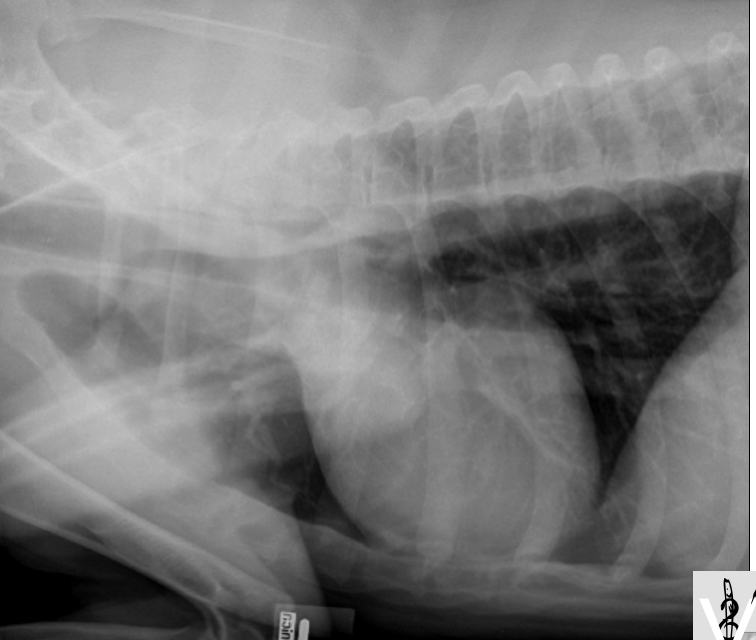

Cas 2: Charlot, un chien Labrador Retriever de 4 ans est présenté pour vomissements répétés depuis 2 jours

A. Obstruction mécanique secondaire à un CÉ

B. Gastroentérite

C. Pancréatite

D. Pyélonéphrite

A